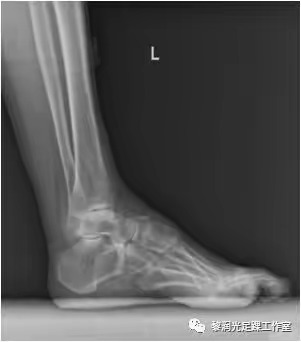

6、足踝影像学评估(X、CT、MRI)